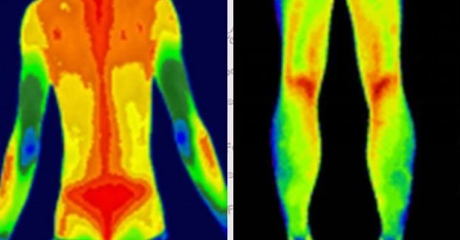

血管病變預(yù)警

自動標(biāo)注肢體溫差>1℃的區(qū)域(提示血栓風(fēng)險)

動態(tài)監(jiān)測糖尿病足微循環(huán)變化

案例:北京某三甲醫(yī)院用其提前7天預(yù)警糖尿病患者足部壞死風(fēng)險

炎癥可視化

智能識別類風(fēng)濕關(guān)節(jié)炎的“梭形熱區(qū)”

量化評估強直性脊柱炎進(jìn)展程度

(插入示意圖:脊柱炎癥熱圖 – 紅色熱區(qū)與MRI病灶位置完全吻合)